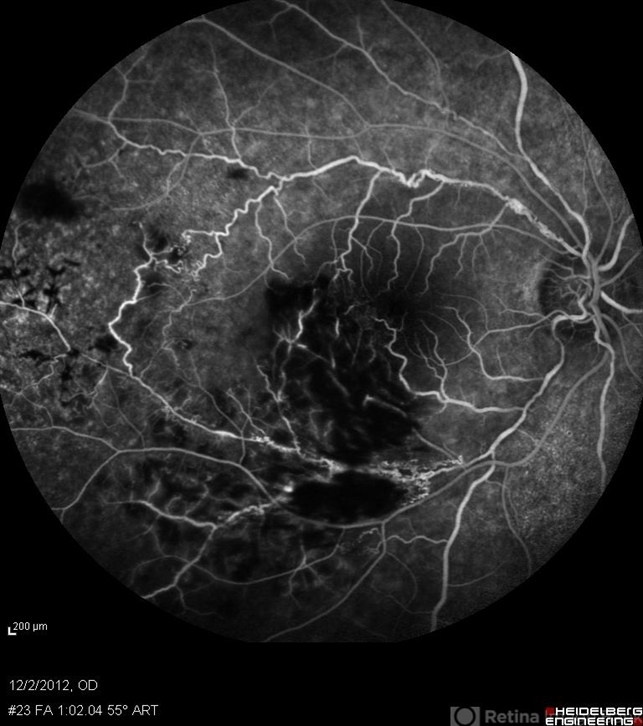

- retinal vasculitis, branch retinal vein occlusion (BRVO)

- Solmaz Shahmohammad, Negah Eye Center, Tehran

- Heidelberg Spectralis

- Mid phase FA of the right eye of a 23-year-old man with retinal vasculitis and branch retinal vein occlusion (BRVO) due to Behcet's disease .